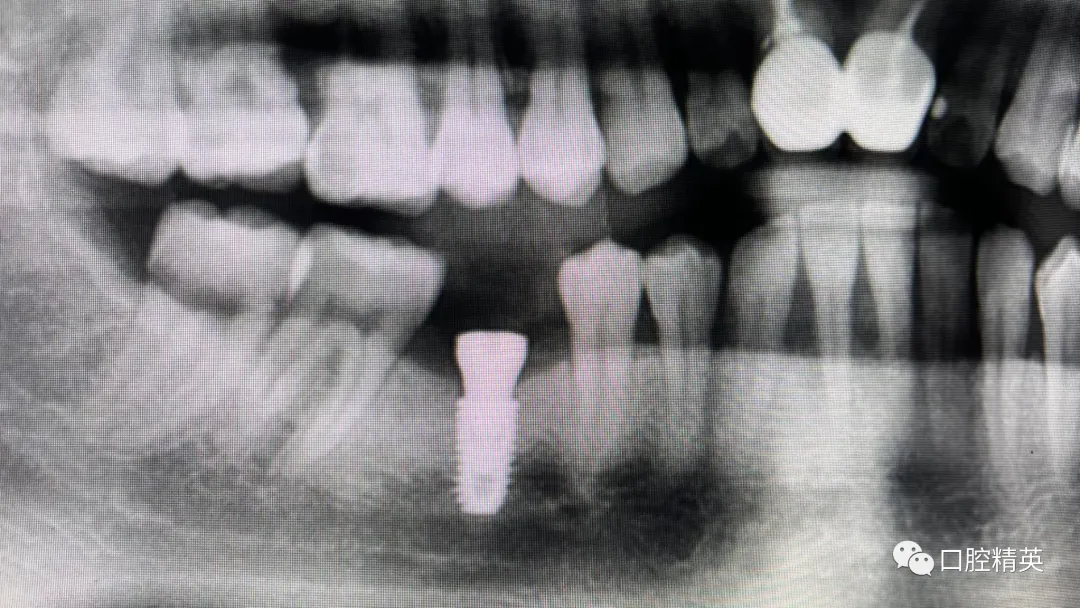

7、种植影像学分析;可以获得骨高度 ,骨宽度信息 ,甚至可以模拟种植体植入位点

六、学员回家后部分病例

七、种植初级往期期部分培训影像